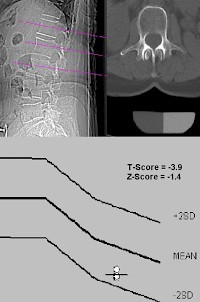

T-Wert

Die verschiedenen Methoden und Geräte sind nicht untereinander vergleichbar. Darum sollten im Befund keine absolute Dichte (außer in der qCT oder pQCT) oder Flächendichte angegeben werden, sondern die Abweichungen vom (alters- und geschlechtsspezifischen) Normalen in Vielfachen einer Standardabweichung (als sogenannter T-Wert, eine dimensionslose Größe).

Nach der gültigen Definition der WHO liegt eine Osteoporose vor, wenn der Messwert der Knochendichtemessung mindestens 2,5 Standardabweichungen unter dem Durchschnitt der geschlechtsgleichen 30-jährigen Gesunden (peak bone mass) liegt, d. h., ein T-Wert ≤ –2,5 vorliegt. Zwischen –1 und –2,5 Standardabweichungen wird von einer reduzierten Knochendichte, einer Osteopenie, gesprochen. Ab einem T Score Wert von −2,6 liegt eine deutlich reduzierte Knochendichte vor und es besteht eine erhöhte Knochenbruchgefahr Osteoporose.

Z-Wert

Der Bezug des T-Werts auf die peak bone mass bringt das Problem mit sich, dass mit zunehmendem Lebensalter immer größere Bevölkerungsanteile als "krank" anzusehen wären; bei den 70-jährigen Frauen fast 50 %. Deshalb wird zusätzlich ein Wert angegeben, der sich auf gesunde Männer bzw. Frauen gleichen Alters bezieht, der Z-Wert.

Ein normaler Z-Wert (> –1) zeigt an, dass die Knochendichte alterstypisch ist. Alter ist keine Krankheit und auch nicht behandelbar; und im Falle von sehr alten Menschen ist auch die erhöhte Frakturgefahr alterstypisch. Osteologen raten deshalb bei niedrigem T-, aber normalem Z-Wert von medikamentösen Therapien (Hormone, Kalzium, Bisphosphonate u. a.) ab und empfehlen vorbeugende Maßnahmen wie Gymnastik, Verzicht auf Sedativa, Abbau von häuslichen Stolperfallen, geeignete Sehhilfen und Gehstützen.

Die Ergebnisse dieser Untersuchungen erhält man immer als Vergleichswerte. Dabei wird der Wert verglichen mit dem Durchschnittswert junger gesunder Personen (T-Wert) oder mit den Durchschnittswerten von Menschen im Alter des Patienten (Z-Wert).